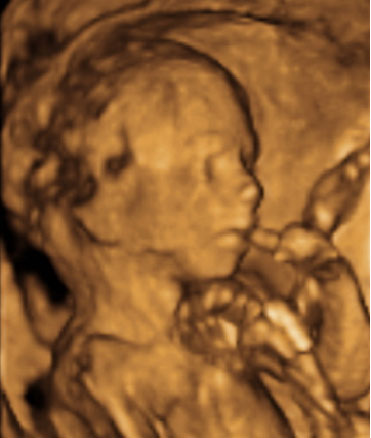

Las ecografías en 4D realizadas en la semana 20 de embarazo permiten ver el sexo femenino del feto con nitidez. En este caso, se ha capturado la imagen de los genitales femeninos, en concreto, la vulva.

Ecografía: Genitales de una niña de 20 semanas

En este ultrasonido, podemos ver la vulva del feto y otros pequeños detalles del sexo fetal.